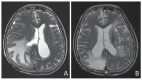

Fig. 4

A: Preoperative T2-weighted magnetic resonance imaging (MRI) showing massive brain edema with a midline shift. B: T2-weighted MRI performed a month after surgery revealing a decrease in the degree of brain edema and an improvement in the midline shift. It also showed removal of the hematoma in the left frontal lobe.